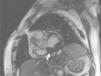

Case reportAn 84-year-old woman, with a history of hypertension and dyslipidemia, was admitted to our institution because of an intracardiac mass. She described a five-month history of shortness of breath on exertion (NYHA functional class III) and peripheral edema. Physical examination revealed a grade III/VI mitral systolic murmur. The electrocardiogram was unremarkable. Laboratory tests results showed no significant alterations. The transthoracic echocardiogram demonstrated a large, round, heterogeneous, echodense mass at the base of the posterior leaflet (Fig. 1). Doppler examination documented severe mitral regurgitation. The three-dimensional transthoracic echocardiogram revealed the mass involving the posterior mitral annulus, distorting it into a more triangular shape (Fig. 2). Three-dimensional transthoracic color flow imaging showed an eccentric mitral regurgitation jet originating from the posteromedial commissure (Fig. 3). The transesophageal echocardiogram confirmed the location of the mass and severe mitral regurgitation (Fig. 4), with two jets identified, one central and the other eccentric, apparently originating from the posteromedial commissure. Cardiac magnetic resonance (CMR) imaging was performed to better evaluate the mass. This showed a hypointense mass in the posterior region of the mitral annulus/basal segment of the inferior wall (Figs. 5 and 6). Rest perfusion CMR demonstrated hypoperfusion of the mass compared to normal myocardium (Fig. 7). Phase-sensitive inversion-recovery CMR showed late gadolinium enhancement in the peripheral margin of the mass (Fig. 8). On the basis of the above findings, a presumptive diagnosis of a centrally liquefied mass containing a high-protein or hemorrhagic content with an inflammatory and/or fibrotic wall was made. A multislice computed tomography (CT) scan of the heart was also performed, demonstrating a relatively homogeneous, high-density mass with foci of calcification (Figs. 9 and 10). A multi-modality imaging approach confirmed the diagnosis of caseous calcification of the posterior mitral annulus.

DiscussionCCMA is a rare evolution of mitral annular calcification.2,3 Echocardiography typically identifies this entity as a round, calcified, echogenic mass.4 CMR reveals a mass between the posterior mitral annulus and adjacent myocardium, with no enhancement after contrast administration and with strong peripheral enhancement 10 minutes after gadolinium administration with the use of the contrast-enhanced inversion-recovery technique.5 CT confirms the calcified aspect of the mass. Histological examination of the inner fluid usually reveals an amorphous, basophilic content, composed of a putty-like admixture of fatty acids, cholesterol, calcium and inflammatory cells, mainly macrophages.4,6 Early recognition of this entity avoids an invasive diagnostic approach, since it is benign and, unlike intracardiac tumors and abscesses, has a favorable prognosis.7 Surgery should be reserved for cases with severe co-existent mitral valve dysfunction, originating from compromised mitral leaflet coaptation secondary to mitral annulus distortion due to CCMA. There are brief references in the literature to possible spontaneous resolution of this entity.8,9 CCMA may rarely be associated with heart rhythm disturbances and systemic embolism.10